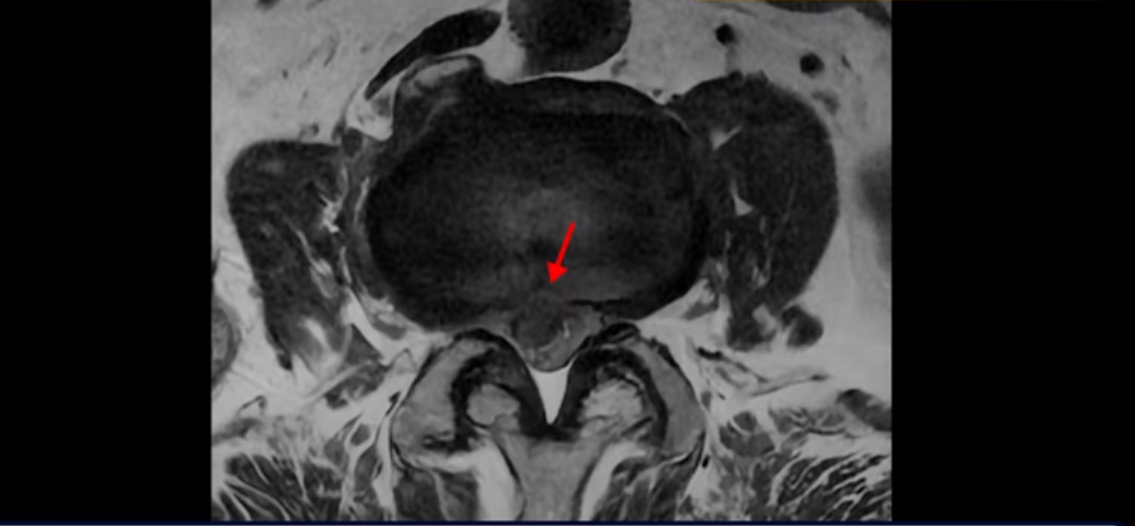

3번 4번에는 척추관협착과 디스크 탈출이 보이고

기립근의 지방화도 심합니다. 또 3번 4번 마디에서는 신경가지가 빠져나가는 추간공이 왼쪽, 오른쪽 모두 많이 좁아져 있습니다.

이런 이유로 이 환자분은 왼쪽 다리는 마비가 생겨 힘이 빠지고 오른쪽 다리에는 심한 방사통이 있어서 휠체어까지 타야 하는 상태가 되었습니다. 이렇게 심하니까 대학병원에서 여러 마디 나사를 박는 유합술을 권유 받으셨는데요.